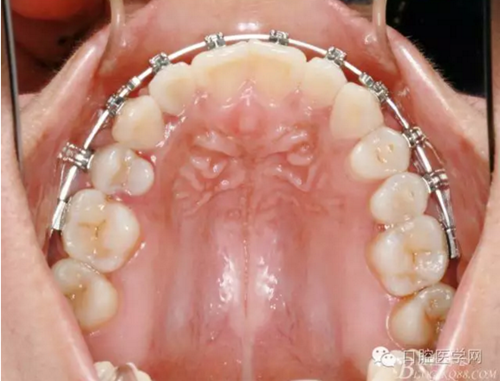

正畸醫(yī)生都想把患者做到“理想頜”,而臨床工作中卻很難如愿;這個(gè)患者到診時(shí),口內(nèi)已經(jīng)有兩顆恒牙缺失;

37,45缺失后,鄰牙近中移動(dòng)占據(jù)了部分牙位;患者要求減少治療費(fèi)用,不做種植修復(fù),那怎么協(xié)調(diào)右側(cè)的咬合關(guān)系?

15是根管治療過(guò)的牙齒,只好忍痛舍去......

在滿足功能的前提下,退而求其次...有時(shí)候,正畸醫(yī)生不得不妥協(xié)。